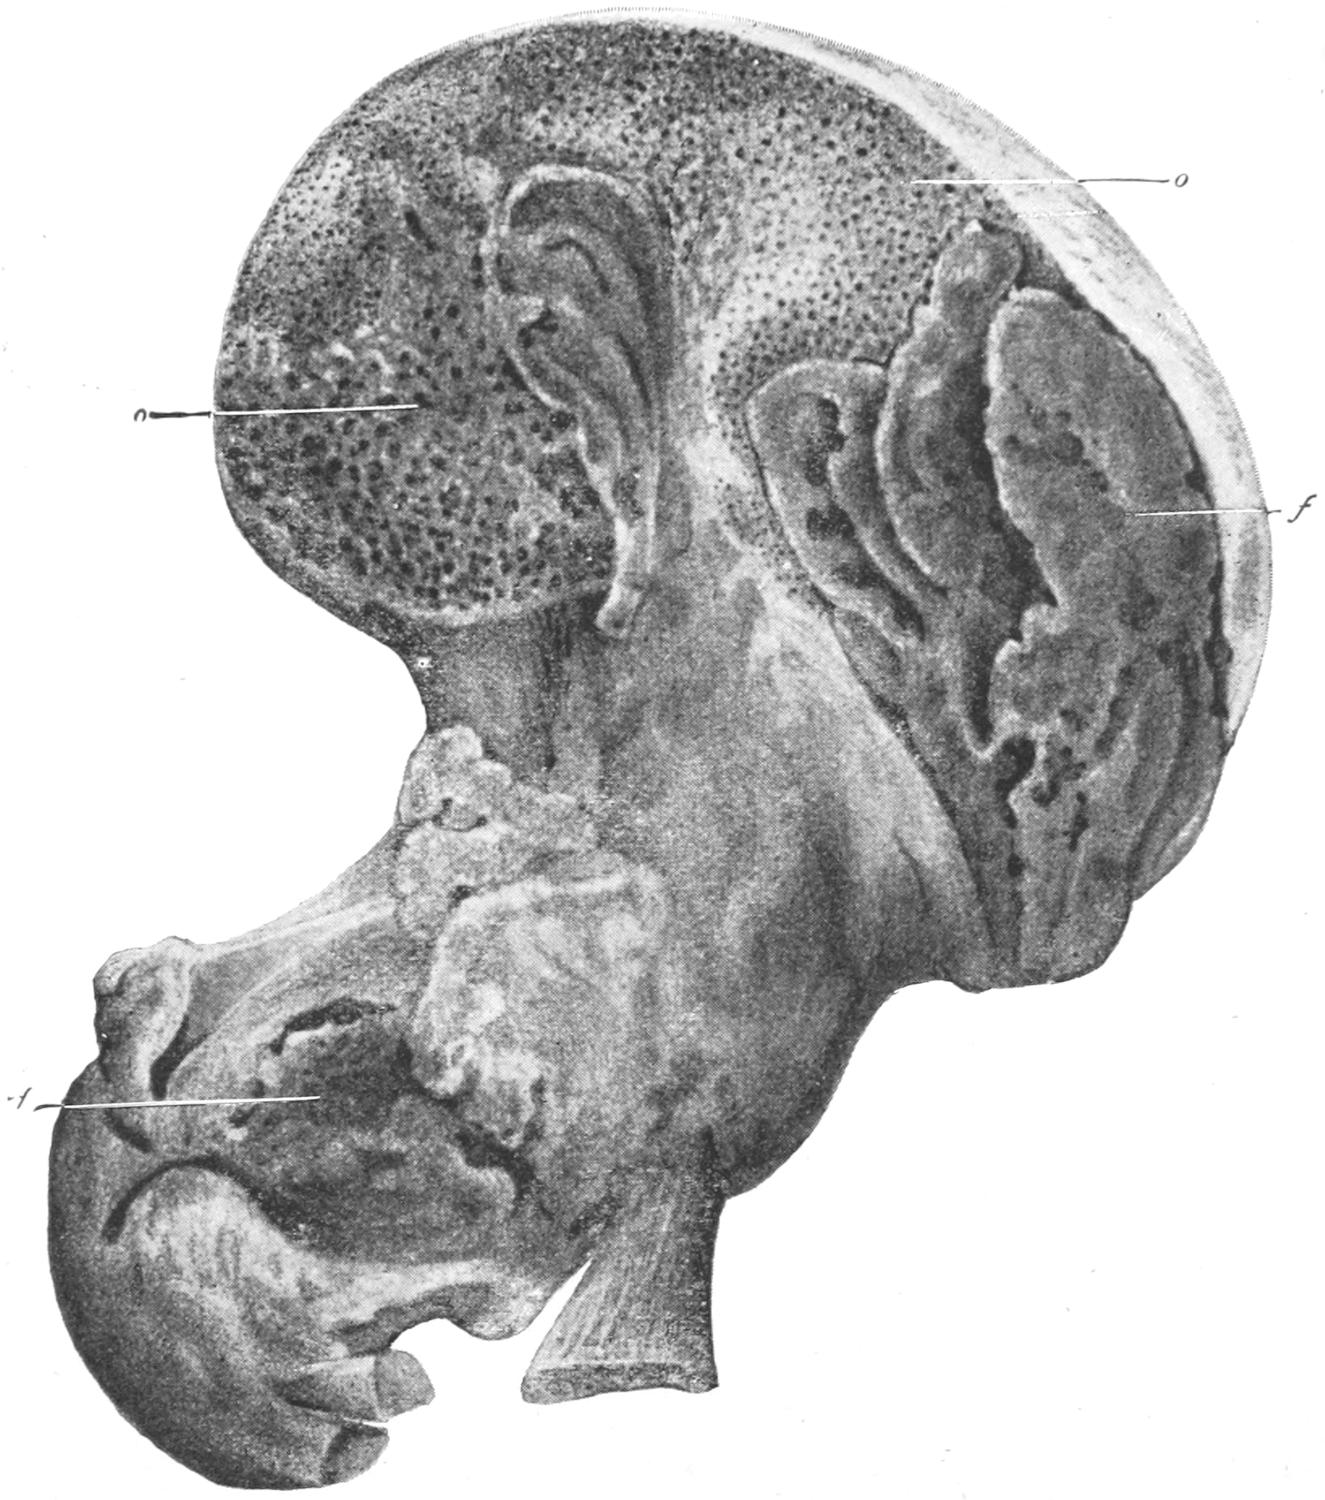

Fig. 1

Congenital hypertrophy: gigantism of both lower extremities. (Case of Dr. Graefe [Sandusky].)